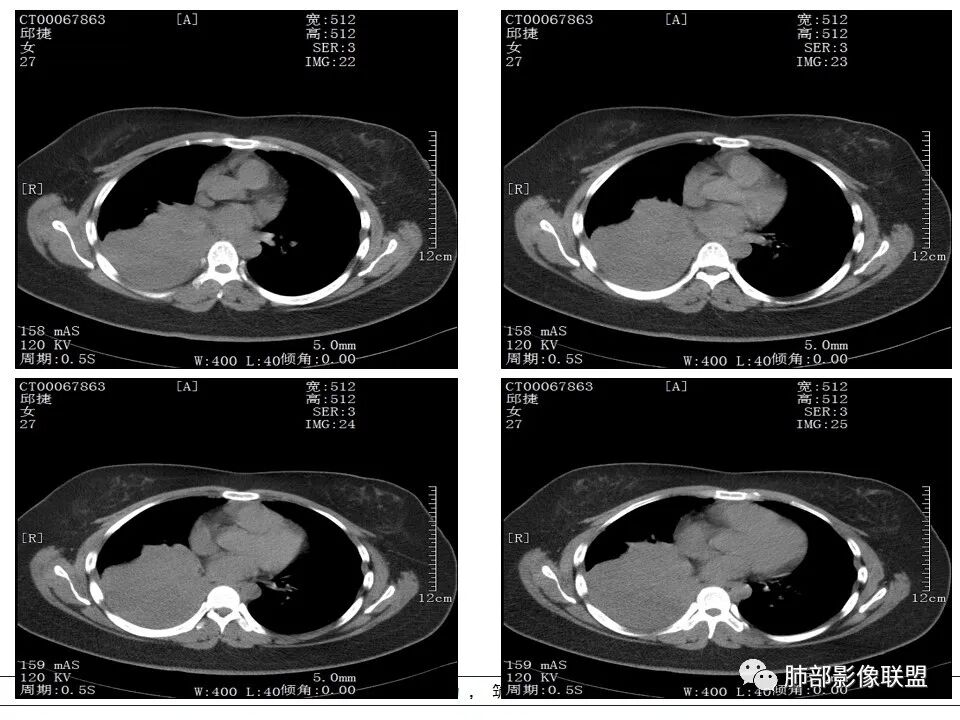

右肺体积缩小,右肺门可见片状影,叶支气管堵塞,呈低密度,无强化,其内似可见点状高密度钙化,病变外周膨隆,右肺下叶大片状致密影,增强后明显强化,其内血管走形自然,右肺下叶呈肺不张改变。纵隔肺门无肿大淋巴结。年轻女性,高热、黄痰来诊。综合考虑:右肺中、下叶综合征合并下叶肺不张,考虑炎性病变,炎性叶支气管阻塞可能性大,早期肺脓肿?结核有点不符合,无胸水,病灶形态太单一。

右肺中叶粘液栓,中叶低密度肿块,密度均匀,延迟强化,右肺下叶不张,考虑炎性病变

女,27岁,右肺下叶支气管闭塞,圆形软组织肿块和不张肺,增强不均匀强化,见片状坏死,多个纵隔淋巴结肿大,无钙化空洞及卫星灶;考虑恶性占位,肺肉瘤或鳞癌合并肺不张,鉴别诊断:结核,肺脓肿

从CT看难度大。女,27岁,发热6天,咳嗽咳痰3天。无呼吸困难。右中间支气管堵塞?右下肺不张,大支气管堵塞常见原因:结核、肿瘤、异物。无呼吸困难,感觉病程较长,肺不张导致的肺功能下降有一定耐受。堵塞支气管似见低密度病灶,强化不明显,粘液表皮样癌?腺样囊性癌?鳞癌?还是结核?有待支气管镜进一步检查。

首先考虑支气管内肿瘤(如类癌、腺样囊性癌),导致阻塞性不涨

右肺下叶支气管闭塞,圆形软组织肿块和不张肺,增强不均匀强化,见片状坏死,多个纵隔淋巴结肿大,无钙化空洞及卫星灶。鳞癌?肺脓肿?

发热咳嗽,右肺下叶可见团块状实变密度影,局部膨隆,并可见胸膜牵拉,相应下叶支气管未见显示,增强后肿块近端呈不均匀强化,可见大片状坏死,内血管略变细,毛糙,周围肺组织支气管内可见粘液栓形成,另纵膈肿大淋巴结,考虑恶性肿瘤,鳞癌,伴阻塞性肺不张,淋巴结转移

临床发热,腹泻,咳黄痰,应该是感染性病变。影像表现为下叶,中叶支气管堵塞,远端支气管内粘液潴留,所属肺组织不张,膈肌明显升高,上叶代偿性肺气肿,增强似乎可见中间段支气管处一个强化结节,考虑中间段支气管占位性病变合并远端支气管粘液潴留,感染可能,肿瘤性质不好定,太年轻,猜一个,粘液表皮样癌

年轻女性,发热6天,咳嗽咳痰三天

CT扫描示右肺下叶支气管堵塞,类圆形大肿块伴胸膜下大片肺实变影,增强扫描类圆形肿块延迟强化,见少量坏死,余实变区增强可见内部血管走行。纵隔见肿大淋巴结。考虑为恶性病变伴右肺下叶肺不张

右下肺门不规则结节强化,并远端支气管粘液栓及大片实变,实变边缘叶间裂膨隆,考虑支气管占位并阻塞性肺炎,涎腺类恶性肿瘤(粘液表)需要鉴别。

右中间支气管阻塞,右肺下叶实变,未见明显支气管空气征,增强中间支气管内病变未见明显强化,纵隔淋巴结增大,偏向恶性病变,结合病史,青年人,肿瘤性病变,支气管表皮样粘液癌可能。

右中间及右下叶支气管堵塞,右下肺不张,下叶堵塞支气管近端见结节状略高密度,远端见管状低密度,堵塞常见原因:结核、肿瘤、异物。强化不明显,粘液表皮样癌?结核?建议支气管镜进一步检查。

患者青年女性,发热6 天,咳嗽、咳痰3天。为黄脓痰。胸部CT:右肺体积稍小,右中间支气管肿物堵塞,中叶、下叶大片实变不张,与正常肺组织分界清楚。增强实变影明显强化,右下肺支气管近心端见类圆形强化结节影,血管纤细,部分支气管显影变细,纵隔淋巴结肿大。结合无呼吸困难症状,病程长。综合考虑低度恶性病变并阻塞性肺炎,类癌可能大,鉴别结核、淋巴瘤。

右肺中下叶实变伴气管腔内粘液栓形成,肺门区见不规则软组织肿块,气管腔狭窄,截断,呈中等强化,纵膈内肿大淋巴结,考虑气管腔内原发肿瘤性病变伴肺实变

右肺体积缩小,右肺巨大低密度肿块并下叶不张,无胸膜尾征,定位肺内,右中间支气管堵塞,肿块内可见粘液栓,不均匀强化,其内血管走行自然,右下肺受侵边缘不整,纵隔内淋巴结肿大,考虑为恶性,年轻女性,粘液表皮样癌首选,其次肉瘤或类癌。